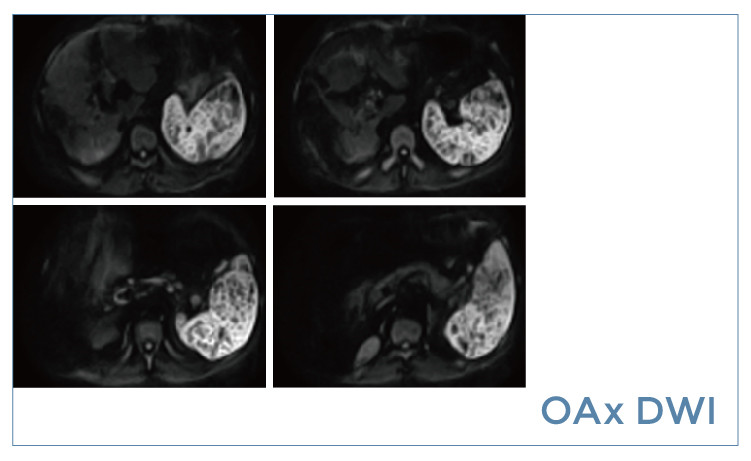

【朗润影像档案】20190517磁共振影像病例结果讨论